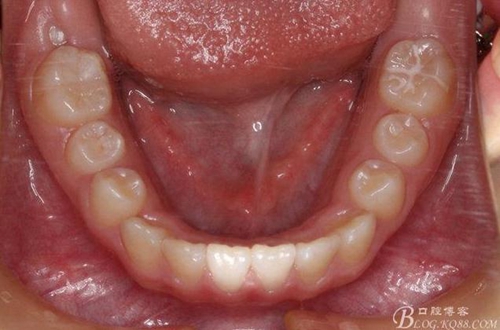

矯治第7個月復(fù)診:磨牙已有咬合接觸。上頜兩個6貼粘貼頰面管,矯治裝置成為真正的“2×4”矯治器。因為上頜兩個3唇側(cè)錯位為完全弓外牙,所以在上頜弓絲上彎制了彎曲進(jìn)行避讓。兩個頰面管的近中設(shè)置了“阻擋曲”,目的是使上頜前牙進(jìn)一步唇移,同時為側(cè)方牙齒的萌出創(chuàng)造空間。停止使用固定式低位唇弓Activator。